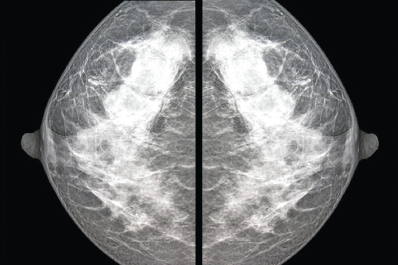

El seno se colocará entre las dos placas de la unidad de mastografía y se aplicará presión para comprimir el tejido que a veces llega a causar molestia pero es necesario para obtener una mejor imagen.

En EDE Satélite también contamos con Mastografía con ultrasonido: